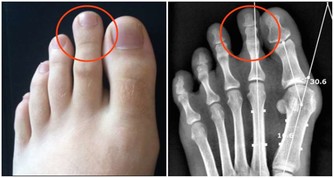

***三、痛風患者。***蝦屬於高嘌呤食物,容易加劇痛風症狀。